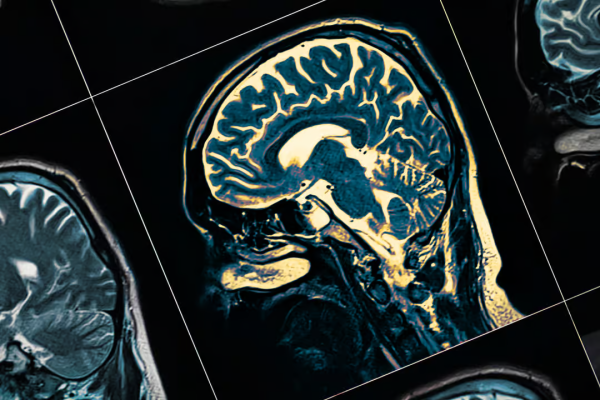

A demência é um dos maiores desafios de saúde pública da atualidade, e estudos apontam que diversos fatores podem influenciar no desenvolvimento da doença. Uma pesquisa do Departamento de Psiquiatria da Universidade de Oxford identificou 13 hábitos e condições que aumentam o risco da demência, sendo que mais da metade deles estão ligados ao estilo de vida. Isso significa que muitas dessas condições podem ser prevenidas ou minimizadas por meio de mudanças comportamentais.

Os pesquisadores identificaram 13 fatores de risco que contribuem para o aumento da probabilidade de desenvolver demência. Entre os principais estão a baixa escolaridade, perda auditiva, hipertensão, sedentarismo e consumo excessivo de álcool. Além disso, condições como diabetes, tabagismo, depressão, trauma craniano e poluição do ar também podem impactar significativamente o desenvolvimento da doença.

O estudo destaca que, embora alguns fatores não possam ser completamente evitados, a maioria deles pode ser controlada por meio de mudanças no estilo de vida e acompanhamento médico adequado.